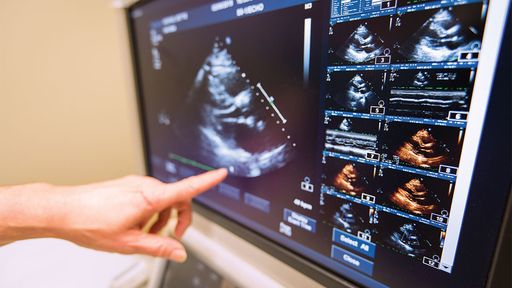

La ecocardiografía se utiliza de forma rutinaria para controlar la función cardíaca y valvular en pacientes con cardiopatías o sospecha de cardiopatías. “Principalmente, analizamos una medida del rendimiento del corazón llamada fracción de eyección [FE], similar a la medición de la potencia del corazón”, dijo el Dr. Erlebacher, quien dirigió el laboratorio de ecocardiografía de Englewood Health durante los últimos 25 años. La FE mide el porcentaje de sangre que se expulsa del corazón con cada latido, que normalmente se mide entre el 55% y el 70%. Una FE que cae en 10 puntos porcentuales y cae por debajo del 53% se ha utilizado como definición de toxicidad cardíaca inducida por quimioterapia. Las máquinas de ecocardiografía avanzadas ahora pueden recrear la cámara de bombeo del ventrículo izquierdo en 3D para obtener una medición de la FE más precisa y reproducible que las técnicas más tradicionales más antiguas. Comprender la FE de un paciente es un paso importante en el diagnóstico y tratamiento de la enfermedad.

La ecocardiografía de seguimiento de motas es una tecnología relativamente nueva, más sensible y capaz de medir la disfunción cardíaca de forma más temprana. “Dentro del músculo cardíaco hay pequeños puntos llamados motas”, explicó el Dr. Erlebacher. “Un software de procesamiento extremadamente avanzado rastrea el movimiento de cada mota individual dentro de la vista del corazón y calcula el movimiento relativo de las motas adyacentes”.

Al medir estas motas en movimiento relativo a medida que el corazón se contrae, se puede obtener una medición de la función regional y global del corazón a través de la deformación longitudinal global (GLS).